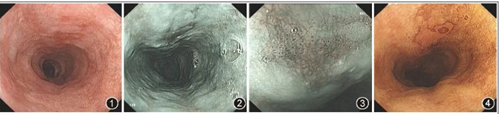

胃鏡檢查是發(fā)現(xiàn)早期食管癌的有效手段

雖然食管癌預(yù)后較差,但食管癌早期患者在接受治療后5年生存率可達(dá)95%,因此高效的篩查與早診早治策略對(duì)于提高食管癌的生存率至關(guān)重要。而胃鏡檢查,作為食管癌篩查的首選方法,在我國(guó)的普及率卻非常之低,主要原因是人們對(duì)自身健康關(guān)注不夠及對(duì)胃鏡檢查的恐懼心理。近年來(lái)我國(guó)食管癌5年合計(jì)相對(duì)生存率有所提高,從20.9%增長(zhǎng)至30.3%,得益于食管癌篩查項(xiàng)目。

早期食管癌通常沒(méi)有特殊癥狀,但有時(shí)會(huì)有刺痛感,在內(nèi)鏡檢查中偶爾得以發(fā)現(xiàn)。食管癌的發(fā)生發(fā)展是一個(gè)長(zhǎng)期的過(guò)程,經(jīng)過(guò)炎癥、癌前病變、早期癌逐漸演進(jìn)至中晚期浸潤(rùn)癌。而在中晚期癌發(fā)生之前,存在長(zhǎng)達(dá)5~10年的演變階段,這為食管癌篩查提供了重要的窗口期。因此,對(duì)食管癌高危人群進(jìn)行篩查和早診早治,是食管癌防治的重要策略與途徑。推薦40歲以上人群進(jìn)行內(nèi)鏡普查;對(duì)于40歲以上合并一項(xiàng)食管癌危險(xiǎn)因素者推薦每5年1次內(nèi)鏡普查,合并多重食管癌危險(xiǎn)因素者建議每1-2年進(jìn)行1次內(nèi)鏡檢查。